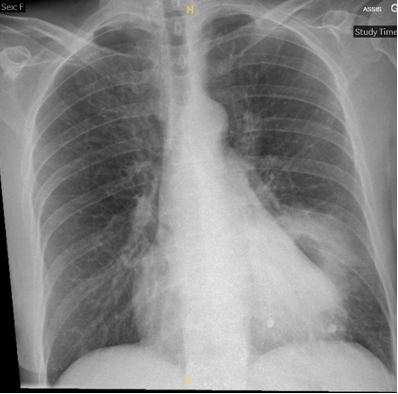

Il s’agit d’une patiente de 59 ans en bonne santé habituelle, sans comorbidité, qui se présente aux urgences suite à un malaise avec chute. Elle présente depuis quelques jours un syndrome grippal avec asthénie, état fébrile et toux. Depuis 2 jours, elle décrit également l’apparition d’une douleur abdominale avec quelques épisodes de diarrhées. Lors de ton examen clinique, la patiente est stable sur le plan hémodynamique mais présente une désaturation à 90% AA et une tachypnée à 25/minutes. Le laboratoire met en évidence un syndrome inflammatoire avec une CRP > 300 mg/dl, sans leucocytose, une hyponatrémie légère ainsi qu’une hypoxémie à la gazométrie. Sur le plan microbiologique, la PCR sur frottis nasopharyngé à la recherche d’une grippe Influenza A est positif, alors que les hémocultures et la culture d’expectorations restent stériles. Il n’y pas d’antigène à Legionella et pneumocoques dans les urines. La radiographie et le scanner thoracique ci-dessous mettent en évidence une lésion pulmonaire excavée.

Une lésion pulmonaire excavée est définie comme une opacité parenchymateuse pulmonaire avec en son sein une hyperclarté avec ou sans niveau hydroaérique et entourée d’une coque.

Lors de la mise en évidence d’une telle lésion à la radiographique, il est préconisé d’effectuer un CT thoracique afin d’orienter le diagnostic. Si l’origine est plutôt infectieuse, une antibiothérapie  d’épreuve peut être mise en place avec un CT de contrôle à distance. En cas d’absence de régression de la lésion excavée, il s’agira d’effectuer une endoscopie bronchique ou ponction trans-thoracique, avec ponction ganglionnaire pour établir un diagnostic histologique.

En ce qui concerne notre patiente, l’évolution clinique et scannographique a été favorable sous traitement de co-amoxiciline.